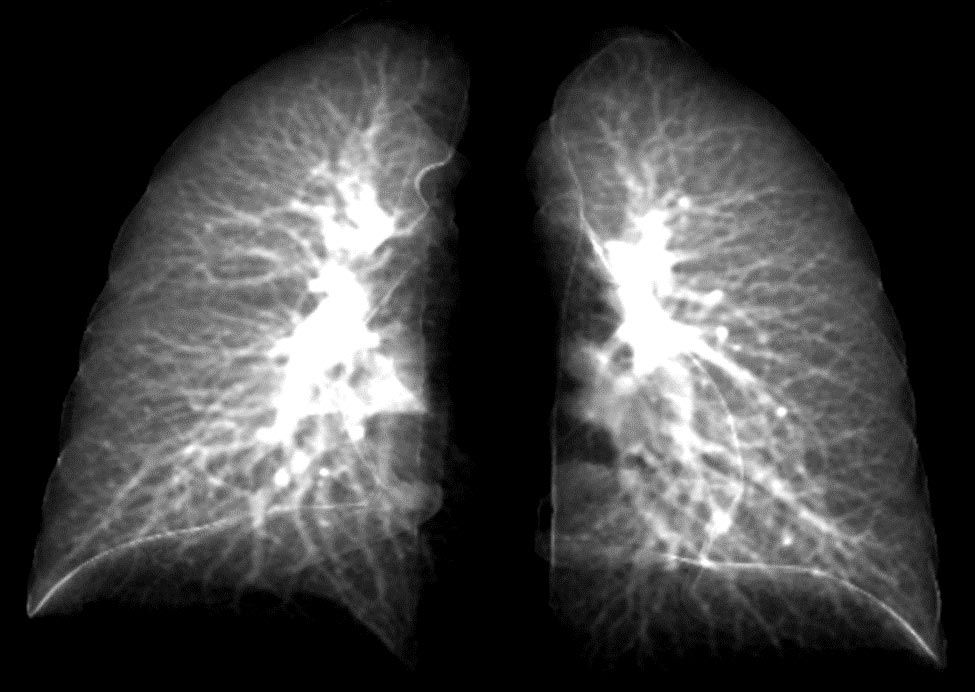

Normal bir göğüs röntgeni, COVID-19'dan kaynaklanan kalıcı solunum semptomlarıyla uğraşan hastalar için sadece az bir miktarını ortaya çıkarabilir. İki boyutlu taramalar, koronavirüsten kaynaklanan risk altındaki akciğer fonksiyonunu tam olarak ayırt edemez. Bu tanı için bilgisayarlı tomografi (BT) taraması adı verilen daha pahalı ve üç boyutlu (3D) olan ayrı bir teknik gereklidir.

Bununla birlikte, dünya genelindeki bir çok klinikte BT tarama ekipmanı çok fazla bulunmamaktadır. Ve bu da COVID-19 hastalarının akciğer fonksiyonları hakkında çok az bilgi sahibi olmalarına neden olur.